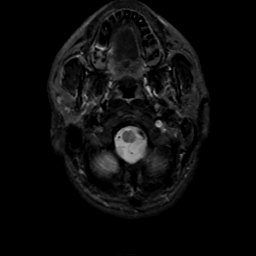

MR Study #7, March 24, 1991 -- Slice #2

[Home][Help][Clinical][Tour 1][Tour 2] Slice 2